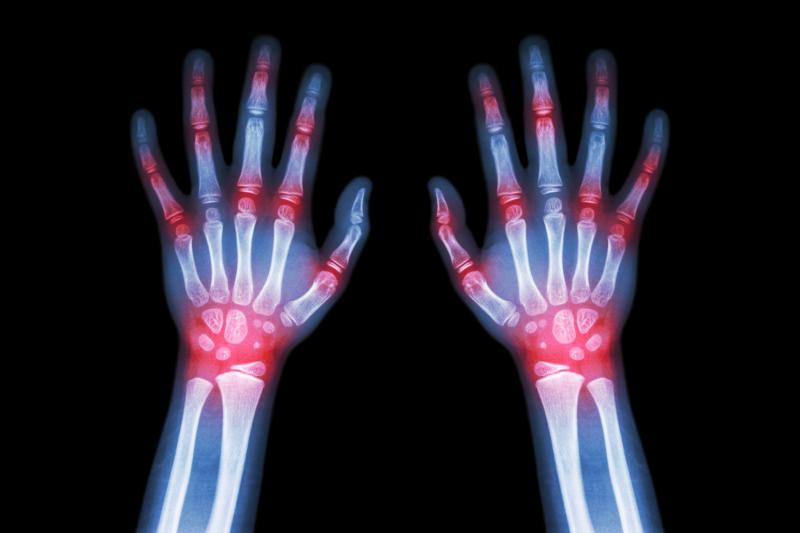

In the treatment of Chinese patients with gout, the use of dotinurad results in a higher response rate compared with febuxostat, according to a phase III study.